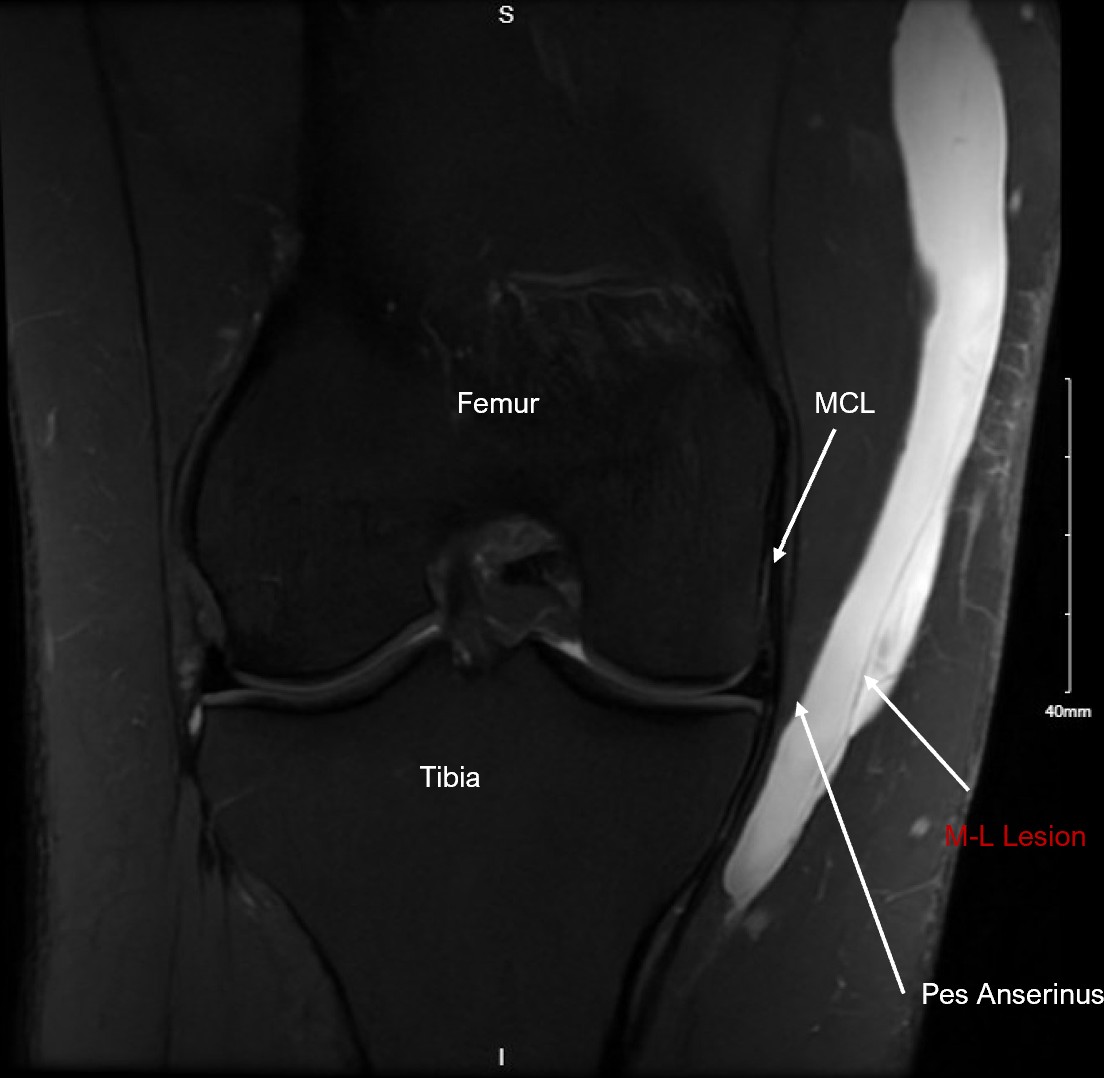

Correlating labeled coronal PD Fat FL MRI of the Morel-Lavallee Lesion.